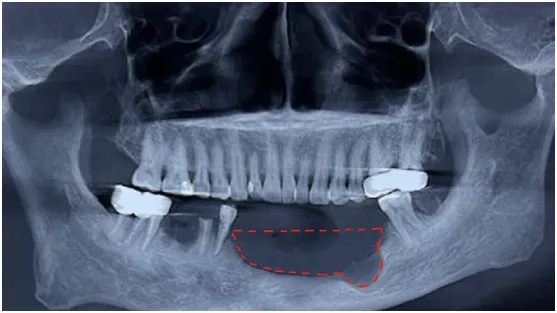

“医生,我牙还没拔,怎么骨头就少了一大块!”如果你也有过这种“骨头被吃掉”的惊悚体验,别慌,你可能遇到了“隐形刺客”——颌骨囊肿。

1. 定期“查户口”:每年洗牙时让医生拍张全景片,囊肿早期像玻璃上的小水珠,一拍就现形。